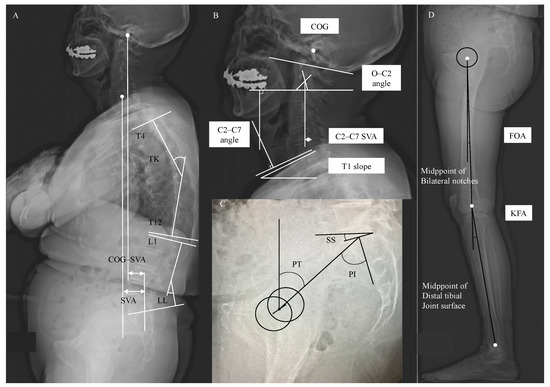

2.2. Image Acquisition and Anatomical Parameters Extraction